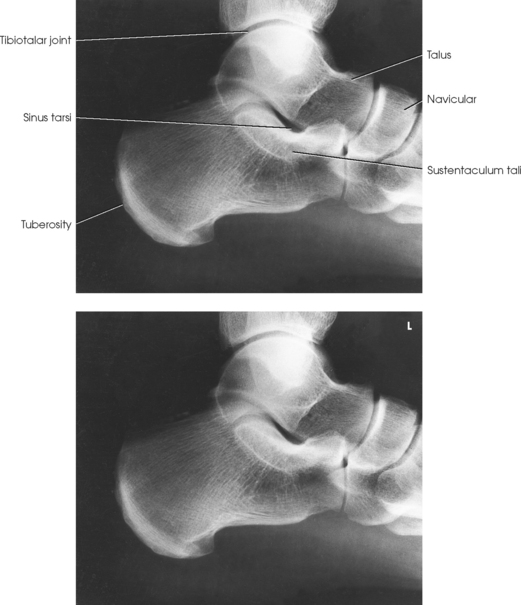

The calcaneus is the largest and strongest tarsal bone (Fig. 6-3). Some texts refer to it as the os calcis. It projects posteriorly and medially at the distal part of the foot. The long axis of the calcaneus is directed inferiorly and forms an angle of approximately 30 degrees. The posterior and inferior portions of the calcaneus contain the posterior tuberosity for attachment of the Achilles tendon. Superiorly, three articular facets join with the talus. They are called the anterior, middle, and posterior facets. Between the middle and posterior talar articular facets is a groove, the calcaneal sulcus, which corresponds to a similar groove on the inferior surface of the talus. Collectively, these sulci constitute the sinus tarsi. The interosseous ligament passes through this sulcus. The medial aspect of the calcaneus extends outward as a shelflike overhang and is termed the sustentaculum tali. The lateral surface of the calcaneus contains the trochlea.

Each of the three parts of the subtalar joint is formed by reciprocally shaped facets on the inferior surface of the talus and the superior surface of the calcaneus. Study of the superior and medial aspects of the calcaneus (see Fig. 6-3) helps the radiographer to understand better the problems involved in radiography of this joint.